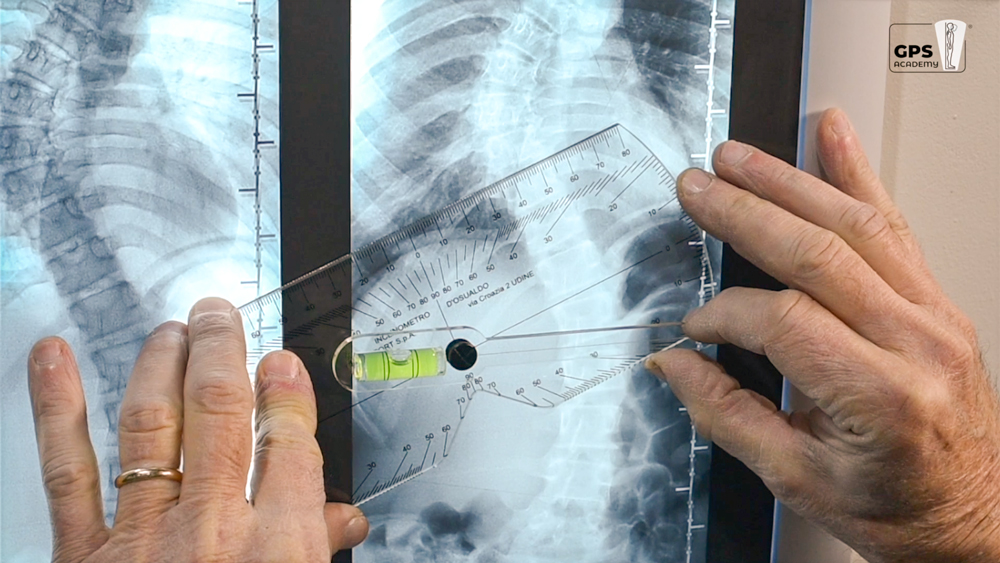

The D'Osualdo inclinometer is a device with two important functions: on one hand the tool estimates the angle of trunk rotation during the Adam’s forward bending test while on the other hand helps measuring the Cobb angle on radiographs. The inclinometer, thus, can be used to evaluate spine curves on the frontal plane (scoliosis) and on the sagittal plane (kyphosis and lordosis).

Measurement on patient - during the forward bending test the patient has to reach the standard position with knees extended, arms hanging and trunk bent forward. The inclinometer is then placed on the back and the rod is moved until the bubble is centred. The clinician can read either immediately the angle of rotation or after the tool removal while fixing the rod between their fingers. The clinician is then able to identify the most rotated vertebrae simply repeating the measurements along the thoracic and lumbar segments.

The Cobb angle is found on radiographs by placing the inclinometer on the spine’s most tilted vertebra above the curve’s apex and then on the most tilted vertebra beneath the apex. The rod bubble has to be centred to determine the angle of inclination. The Cobb angle is found adding the two angles together.

The inclinometer is very useful for quickly identifying the most inclined vertebrae on the X-ray.

The inclinometer is an almost rectangular-shaped device made of plexiglas with a goniometric scale. The tool has a small, rotating rod on its centre with a bubble on its shorter extremity. The longest side of the rod indicates the estimated values of rotation or inclination on the goniometric scale. If spinous processes are particularly protruding, the inclinometer can still be used placing its central recess over them.